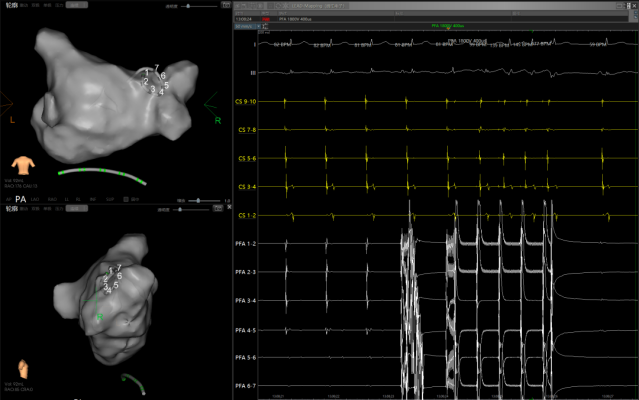

再通过11F鞘经8.5F固定弯鞘在ICE指引下顺利完成房间隔穿刺,之后通过ICE导管在LEAD-MAPPING三维标测系统中建立左心房及肺静脉三维模型,使用PFA导管依次行肺静脉口部消融。

(图中红色区域为瘢痕区、紫色区域为正常电压区)

整个手术步骤包括冠状静脉窦电极放置、房间隔穿刺、消融导管导航及消融治疗全过程均未进行X线透视,实现完全零射线下手术操作。

(房颤→消融→正常心律)